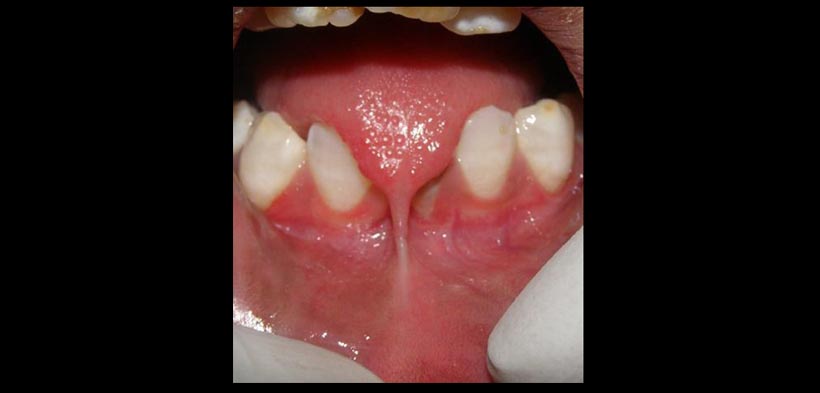

Fig. 3. Postquirúrgico del tratamiento de frenillo lingual.